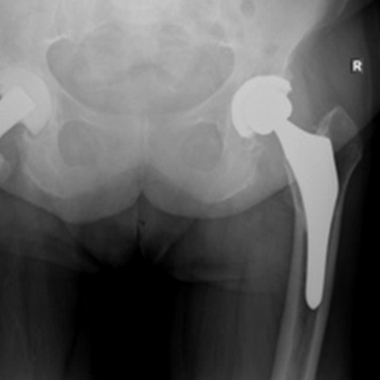

Fast Track Recovery Protocol to nowoczesne podejście do leczenia operacyjnego, które znacząco przyspiesza powrót pacjenta do pełnej sprawności po zabiegach, takich jak endoprotezoplastyka stawu biodrowego czy kolanowego.

Zastosowanie protokołu Fast Track w chirurgii stawu biodrowego i kolanowego pozwala na:

znaczne ograniczenie bólu pooperacyjnego,

zmniejszenie ryzyka powikłań,

skrócenie pobytu w szpitalu do minimum (nawet do 1–2 dni),

szybszy powrót do samodzielności i pracy zawodowej.